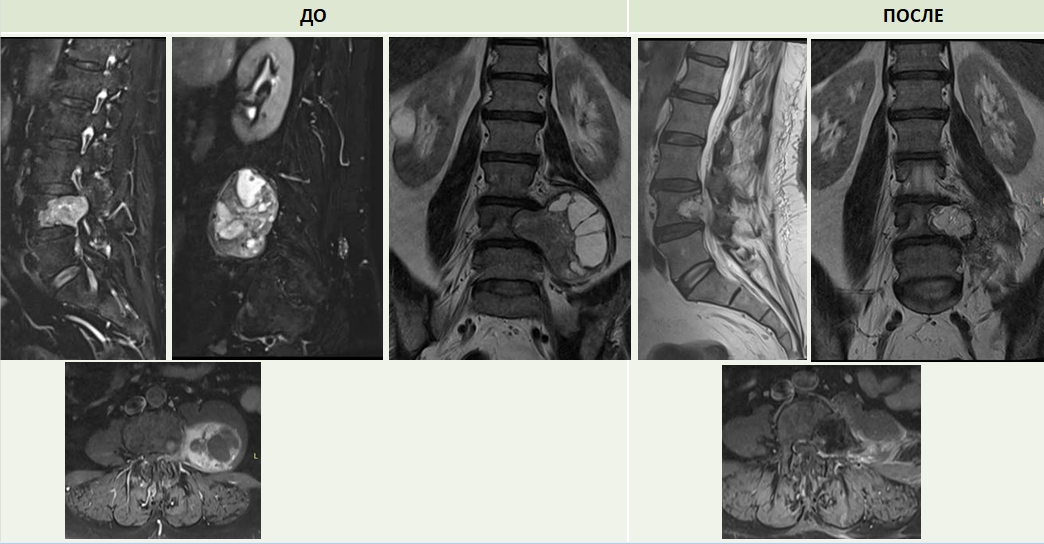

Второй случай связан с оперативным лечением 61-летней пациентки из Кургана с объемными образованиями в поджелудочной железе и позвоночнике. У женщины были жалобы на трудности при ходьбе, подъеме по лестнице, смене положения «сидя-стоя», она испытывала сильный болевой синдром.

МРТ-обследование показало, что опухоль в позвоночном канале располагалась на уровне 4 поясничного позвонка слева паравертебрально. Размер новообразования составлял 8 см * 6 см. За хирургическое лечение сложного случая вновь взялись врачи Клиники патологии позвоночника и редких заболеваний Центра Илизарова: Алексей Евсюков и Константин Григорович.

- Первым этапом выполнили открытую биопсию для подтверждения опухолевого процесса, а далее перешли к удалению опухоли. Сложность операции заключалась в том, что образование располагалось как снаружи позвоночного канала, так и внутри него. Это изначально предполагало два различных доступа для тотального удаления опухоли. Нам удалось выполнить оперативное лечение из одного доступа. Под нейрофизиологическим контролем было выполнено микрохирургическое удаление новообразования спинномозгового нерва, - рассказал врач-нейрохирург Константин Григорович.

После операции болевой синдром в течение двух дней был полностью купирован, смена положения тела и ходьба не вызывают дискомфорта у пациентки.